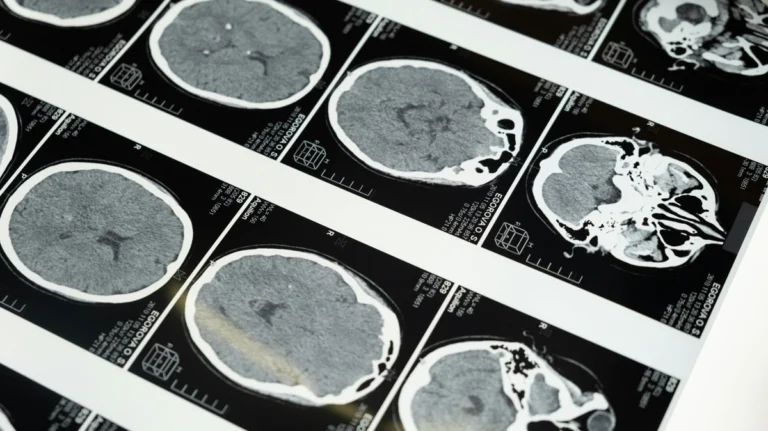

USC Keck School of Medicine tarafından yürütülen yeni çalışma, Alzheimer riskinin değerlendirilmesinde beyin damar sağlığının daha erken ve daha erişilebilir bir gösterge olabileceğini ortaya koydu. Araştırmada yaşlı bireylerde transkraniyal Doppler ultrason ve yakın kızılötesi spektroskopi ile beyin kan akımı ve oksijenlenme parametreleri incelendi; bu veriler amiloid birikimi ve hipokampus hacmi gibi bilinen risk göstergeleriyle karşılaştırıldı.

Bulgular, damar fonksiyonu daha iyi olan katılımcılarda Alzheimer ile ilişkili biyolojik risk profilinin daha olumlu seyrettiğini gösterdi. Özellikle kan akımının düzenlenmesi ve oksijen iletimi kapasitesinin korunması, daha düşük risk göstergeleriyle birlikte gözlendi. Bu sonuç, Alzheimer patofizyolojisinde yalnızca amiloid/tau ekseninin değil, vasküler sistemin de önemli bir rol oynadığını güçlendiriyor.

Çalışmanın öne çıkan tarafı, kullanılan yöntemlerin non-invaziv ve görece düşük maliyetli olması. PET veya ileri MR protokollerine kıyasla daha pratik uygulanabilen bu ölçümler, geniş kitlelerde erken risk taraması için gelecek vadeden bir seçenek olarak değerlendiriliyor. Bununla birlikte araştırmacılar, mevcut verinin kesitsel olduğunu ve nedensellik için uzunlamasına takip çalışmalarına ihtiyaç duyulduğunu vurguluyor.